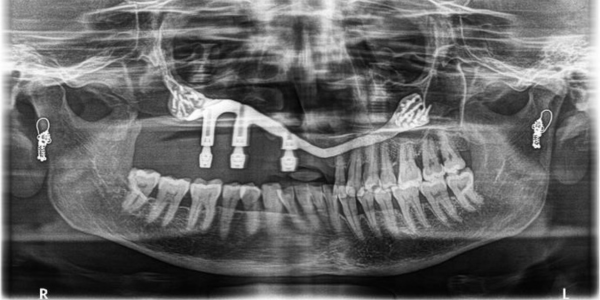

Approximately one year later, Dr. Alka Trymbake collaborated with the design team at 3D Incredible to create and place a patient-specific implant. This implant was tailored to reconstruct the lost maxillary bone, aiming to enhance both facial aesthetics and functional restoration.

3D Incredible provided Patient specific Maxillary implant with screw retained abutment projection for hybrid dental prosthesis. Read more

Implant was manufactured under ISO 13485 guidelines & evaluated to give an accurate fit & utmost safety. Once the resection was done, customized implant from 3D Incredible was implanted.

Implant was manufactured using Ti6Al4V-ELI grade 23, a biocompatible material, as per anatomical requirement, and bone thickness. Read more